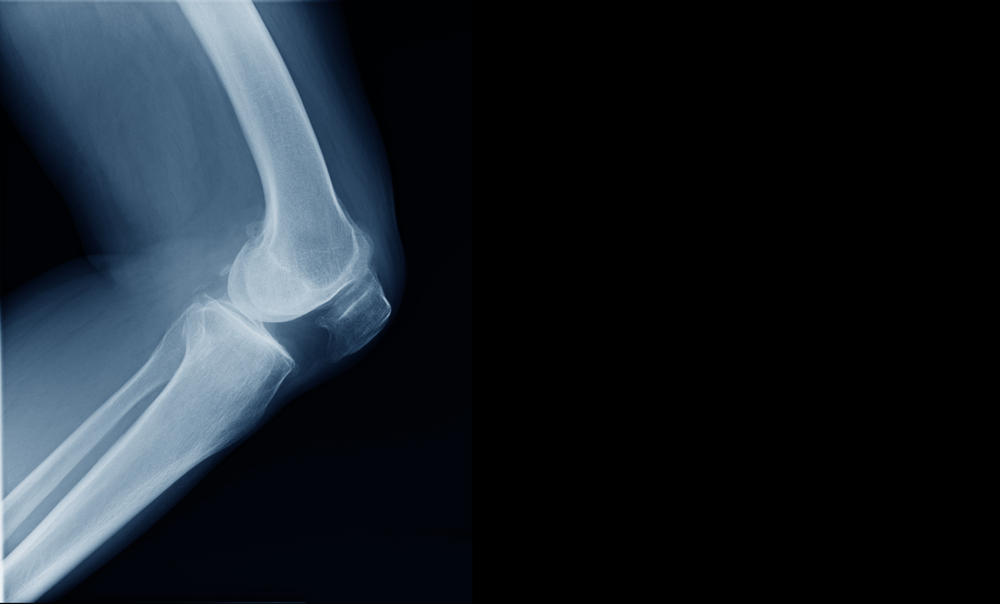

Can An X-ray Show Knee Pain?

X-rays are useful for identifying certain structural issues within the knee joint, such as fractures, dislocations, bone spurs, and signs of osteoarthritis. However, X-rays typically do not show soft tissue problems, such as ligament or cartilage injuries, which are common causes of knee pain. Therefore, while an X-ray can provide valuable information about the bones in the knee joint and any obvious abnormalities, it may not always directly reveal the cause of knee pain.